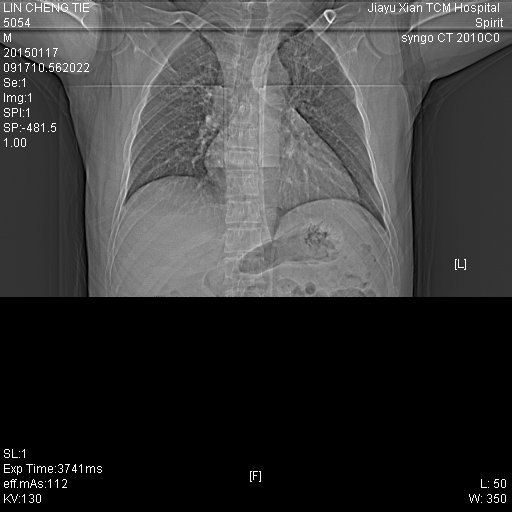

CT49772:男.44岁.咳嗽.胸部不适

两上肺及右肺下叶背段均可见班片结节索条影,两侧胸膜轻度增厚,心影稍大,考虑两肺继发性结核可能性大。

考虑双肺陈旧性肺结核 间质性炎症

还是考虑结核,结合临床症状还有实验室检查~

双肺结核

有改化灶属于结核。

支持两上肺继性性肺结核

支持两肺继发性肺结核伴部分纤维化